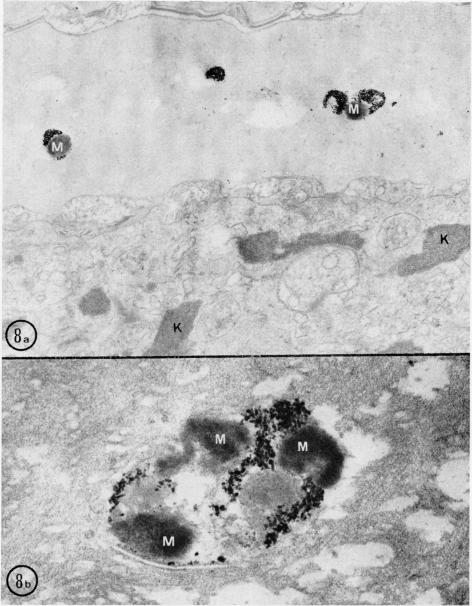

Melanocyte-keratinocyte interactions in vivo: the fate of melanosomes.